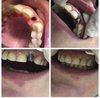

Лечение,удаление,протезирование,имплантация

Стоматолог : Терапевт,Ортопед ;Хирург

Терапевт,Ортопед,Хирург-имплантолог

Полный спектр стоматологических услуг

Весь перечень стоматологических услуг